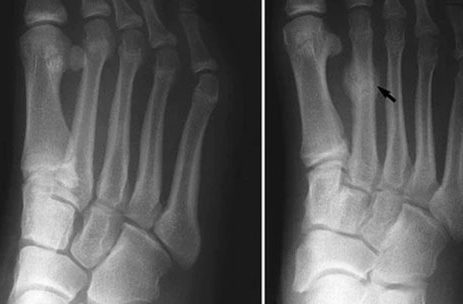

Stress Fracture

A Stress Fracture is an injury to the foot bones that happens over time due to overuse instead of a sudden, sharp blow. It is also sometimes known as a hairline fracture and happens most often in the Metatarsal bones. WHAT CAUSES A STRESS FRACTURE? A stress fracture occurs when the foot muscles because exhausted by repeated activity and motion and can no longer absorb the shock and pressure. The bones then take on the repeated pressure and stress which causes hairline fractures to occur over time. HOW DO I KNOW IF I HAVE A STRESS FRACTURE? WHAT ARE THE SYMPTOMS OF A STRESS...